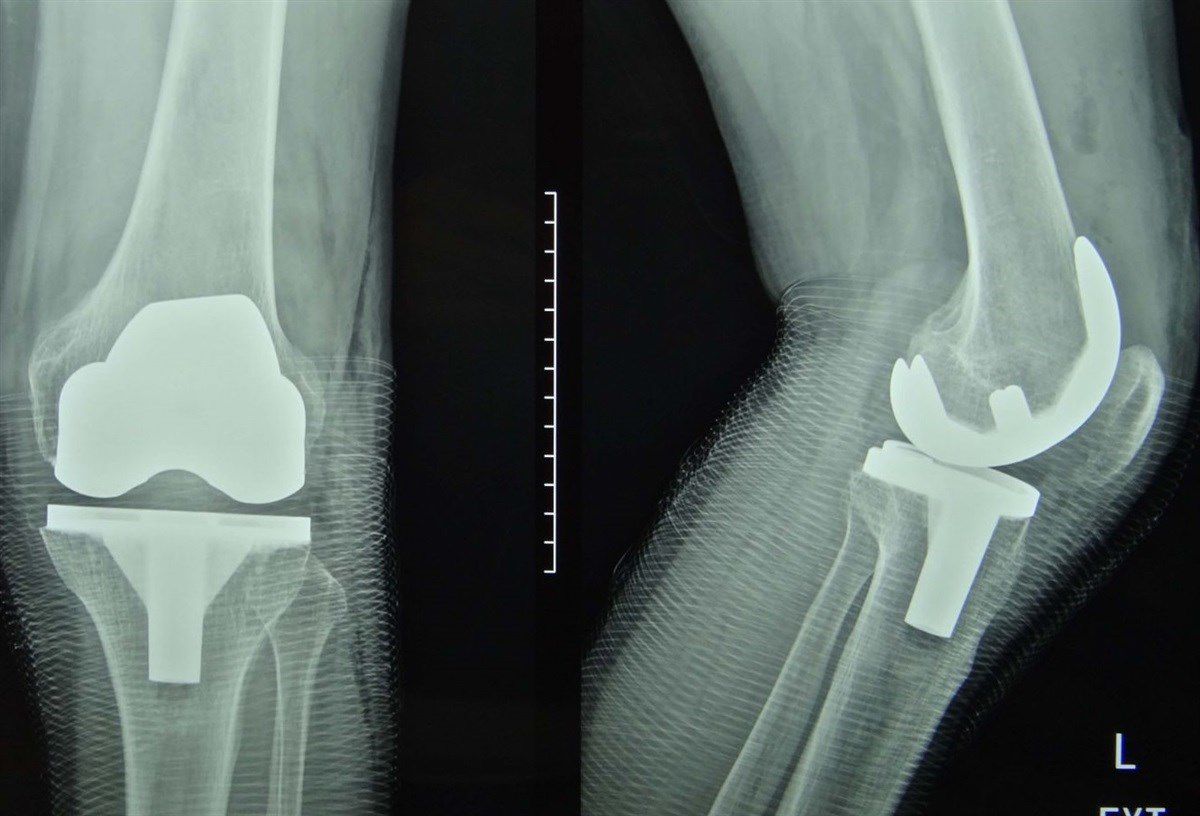

Операция проводится под общей или спинальной анестезией. Хирург удаляет поврежденные поверхности коленного сустава и устанавливает на их место искусственный имплант, состоящий из металлических и полимерных компонентов. Существуют различные типы имплантов, подбираемые индивидуально в зависимости от характера повреждения и анатомических особенностей пациента. После операции на колено накладывается повязка.